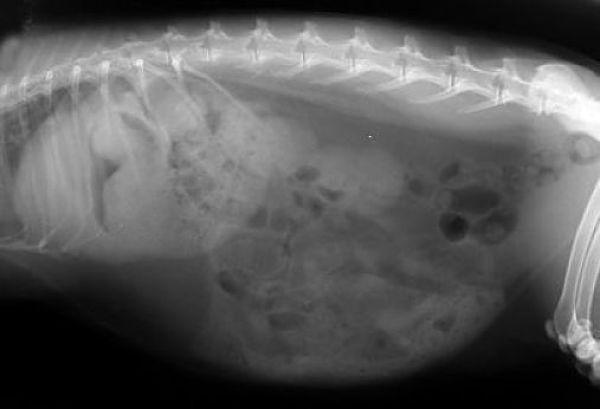

6.- G.I. Stasis

enfermedades-de-los-conejos-6

Esencialmente es una ralentización o paralización del tracto digestivo. La estasis gastrointestinal es una enfermedad peligrosa y a menudo mortal. Los signos pueden incluir la falta excrementos fecales, falta de apetito, no tomar agua, abdomen hinchado y apatía general. Si su conejo exhibe estos síntomas, debe ser evaluado inmediatamente por un veterinario.

Hay una gama de opciones de tratamiento para G.I. estasis que incluyen cirugía, líquidos orales, heno de libre elección, masaje abdominal, y simeticona en gotas o tabletas. El curso del tratamiento dependerá de si una obstrucción intestinal está implicada.

La prevención de G.I. estasis en sus conejos es ideal. Proporcionar una dieta alta en fibra, incluyendo un montón de heno y un alto contenido de fibra en pellets. Esto junto con un suministro ilimitado de agua dulce ayuda a prevenir esta enfermedad. Las verduras frescas también pueden ser una adición beneficiosa a la dieta del conejo.